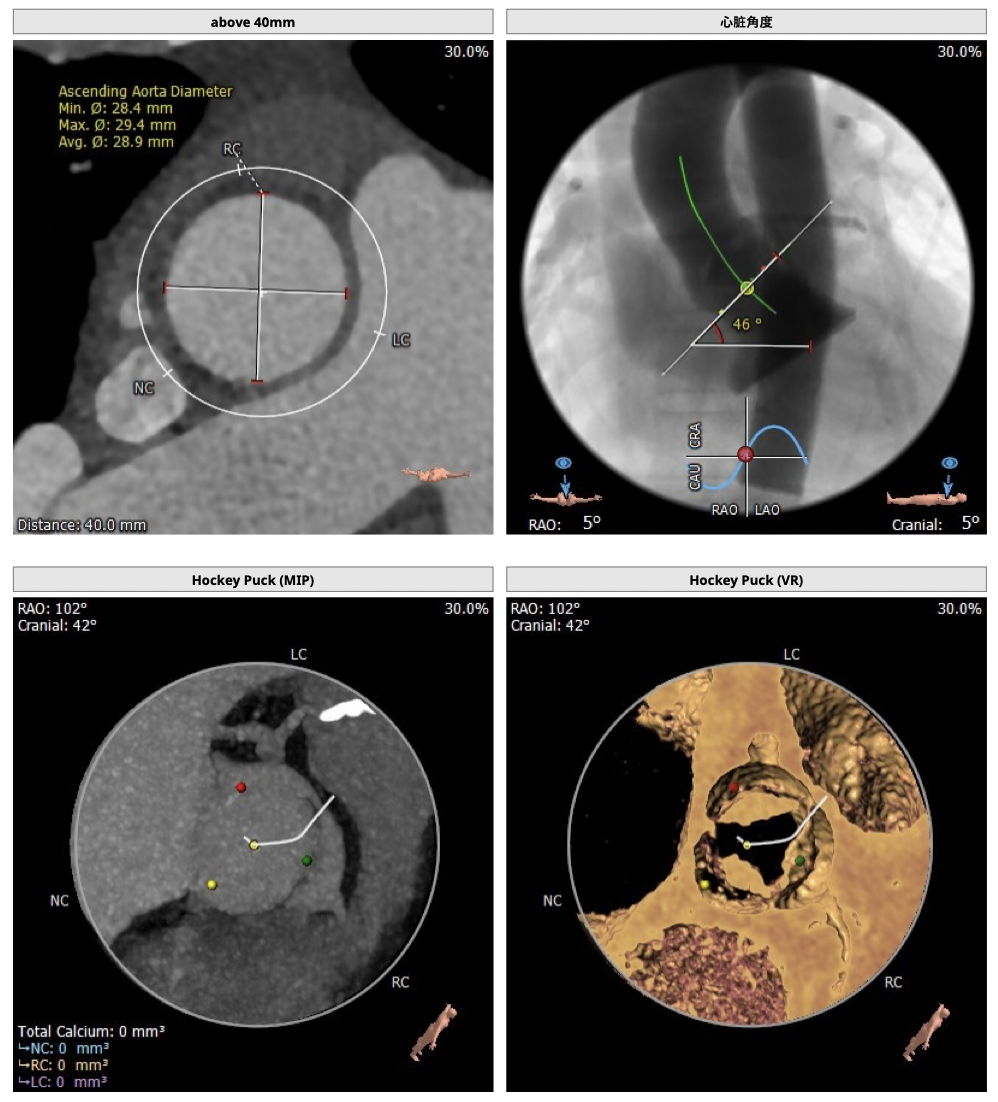

CT检查

②主动脉根部钙化较轻,瓣叶肥厚,各交界缘不同程度粘连,瓣膜释放后具有瓣周漏风险;

③左冠高度不高,且瓣叶冗长,达冠脉开口层面,且冠脉存在狭窄,存在冠脉阻塞的风险;

确保冠脉安全,拟采取PCI+TAVR一站式手术策略,因患者右侧股动脉钙化严重、入路狭窄,拟采取无鞘法从右股动脉穿刺入路,选用20mm球囊预扩、L23号VenusA-Valve瓣膜、采用VenusA-Plus输送系统确保瓣膜的精确释放,瓣膜释放后结合造影和超声情况,决定是否后扩。